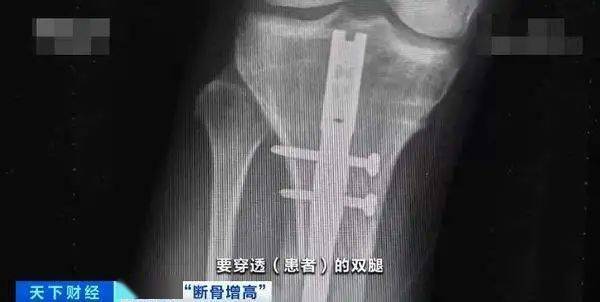

顾名思义 , 断骨增高就是先把腿骨切断 , 然后通过外固定器刺激软骨细胞再生 , 从而让骨骼二次发育 , 最后在长到预期高度后 , 将设备取出让身高固定 。

由于断骨增高术存在较高的医疗风险 , 我国官方早在2006年10月就明令禁止其用于 「 医疗美容项目」。 当然 , 国内依然有部分机构本着 「 人道主义关怀」, 秘密使用着这项禁术 。